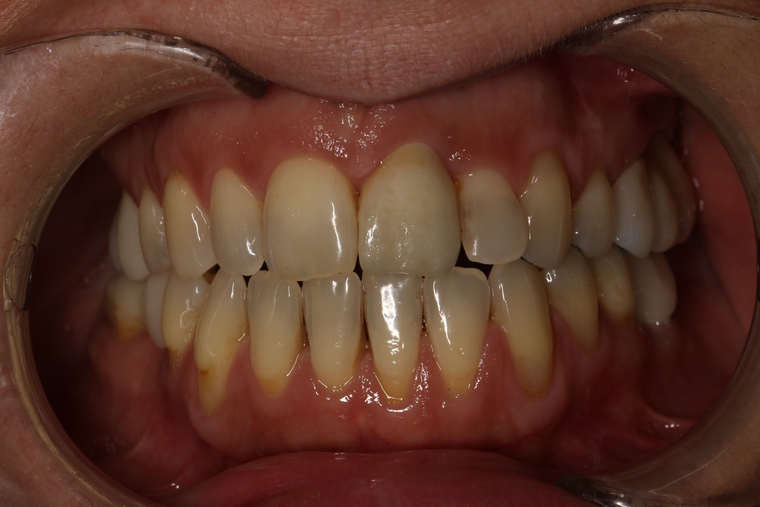

Ein Tätigkeitsschwerpunkt unserer Praxis in Salzburg ist die Implantologie. Wenn ein Zahn fehlt oder entfernt werden muss, sollte immer die Möglichkeit der Implantation im Vordergrund stehen. Ein Implantat verhält sich von den Eigenschaften genau so wie ein natürlicher Zahn. Egal ob nur ein einzelner Zahn vom Zahnarzt ersetzt werden muss oder ein ganzer Kiefer mit festsitzendem Zahnersatz versorgt werden soll, wir finden für Sie eine Möglichkeit, auch wenn die Voraussetzungen ausweglos erscheinen. Wenn möglich versorgen wir unsere Patienten mit Keramikimplantaten. Diese sind immun-neutral und können sehr oft direkt bei der Zahnextraktion eingesetzt werden. Für unsere Patienten ist daher meist nur ein operativer Eingriff notwendig!